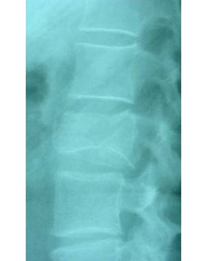

Comparació pre- i post-operatoria d’una cifopastia cementada

Dona, edat 55 anys, fractura aixafament dret de L2

Abans 1

Abans 2